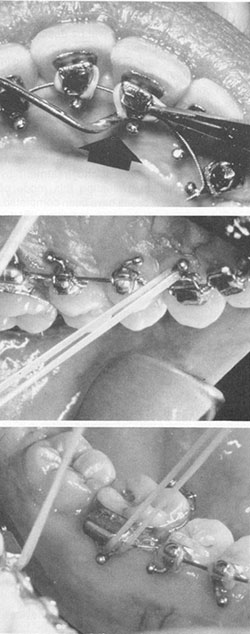

The Lingual Task Force was established in December 1980 to provide additional input on design considerations and to expand the treatment modalities. Ball hooks were added to all lingual brackets at this time. Ball hooks, while aiding greatly in placing elastic ligatures and elastics (Fig. 8), can cause gingival hyperplasia.

Fig. 8 Ball hooks facilitate placement of elastic ligatures and intermaxillary elastics.